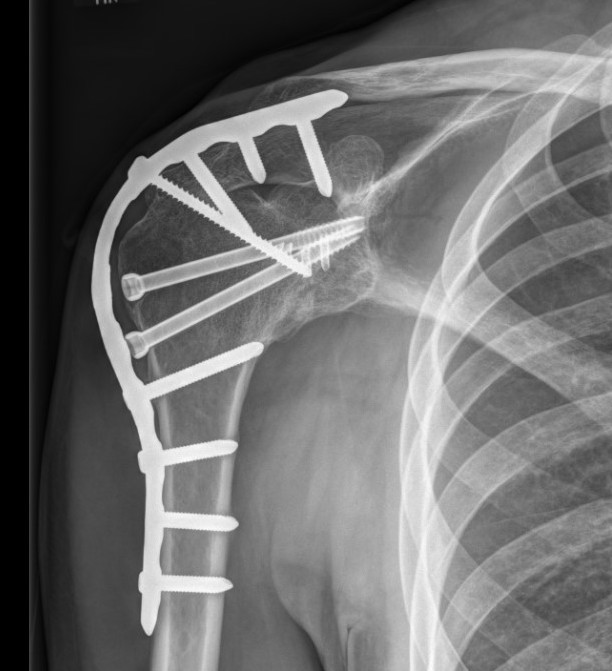

Intra-articular - glenohumeral compression screws +/- acromiohumeral screws

Extra-articular - plate along spine of scapula / acromion and lateral humerus

Combined

- supplement with pelvic reconstruction 12 - 14 hole plate scapular spine / acromion / humerus